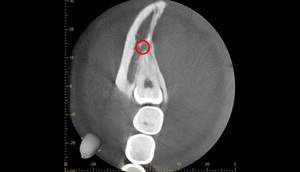

3ヶ月のCT画像①

麻布十番歯科での1回目の親知らず抜歯から3ヶ月後のCT画像①

3ヶ月のCT画像②

麻布十番歯科での1回目の親知らず抜歯から3ヶ月後のCT画像②

1回目から3ヶ月待ちました。下歯槽神経の位置が根の先から離れているのが確認できます。

これで下歯槽神経を損傷させることなく、親知らずの抜歯を行うことができます。